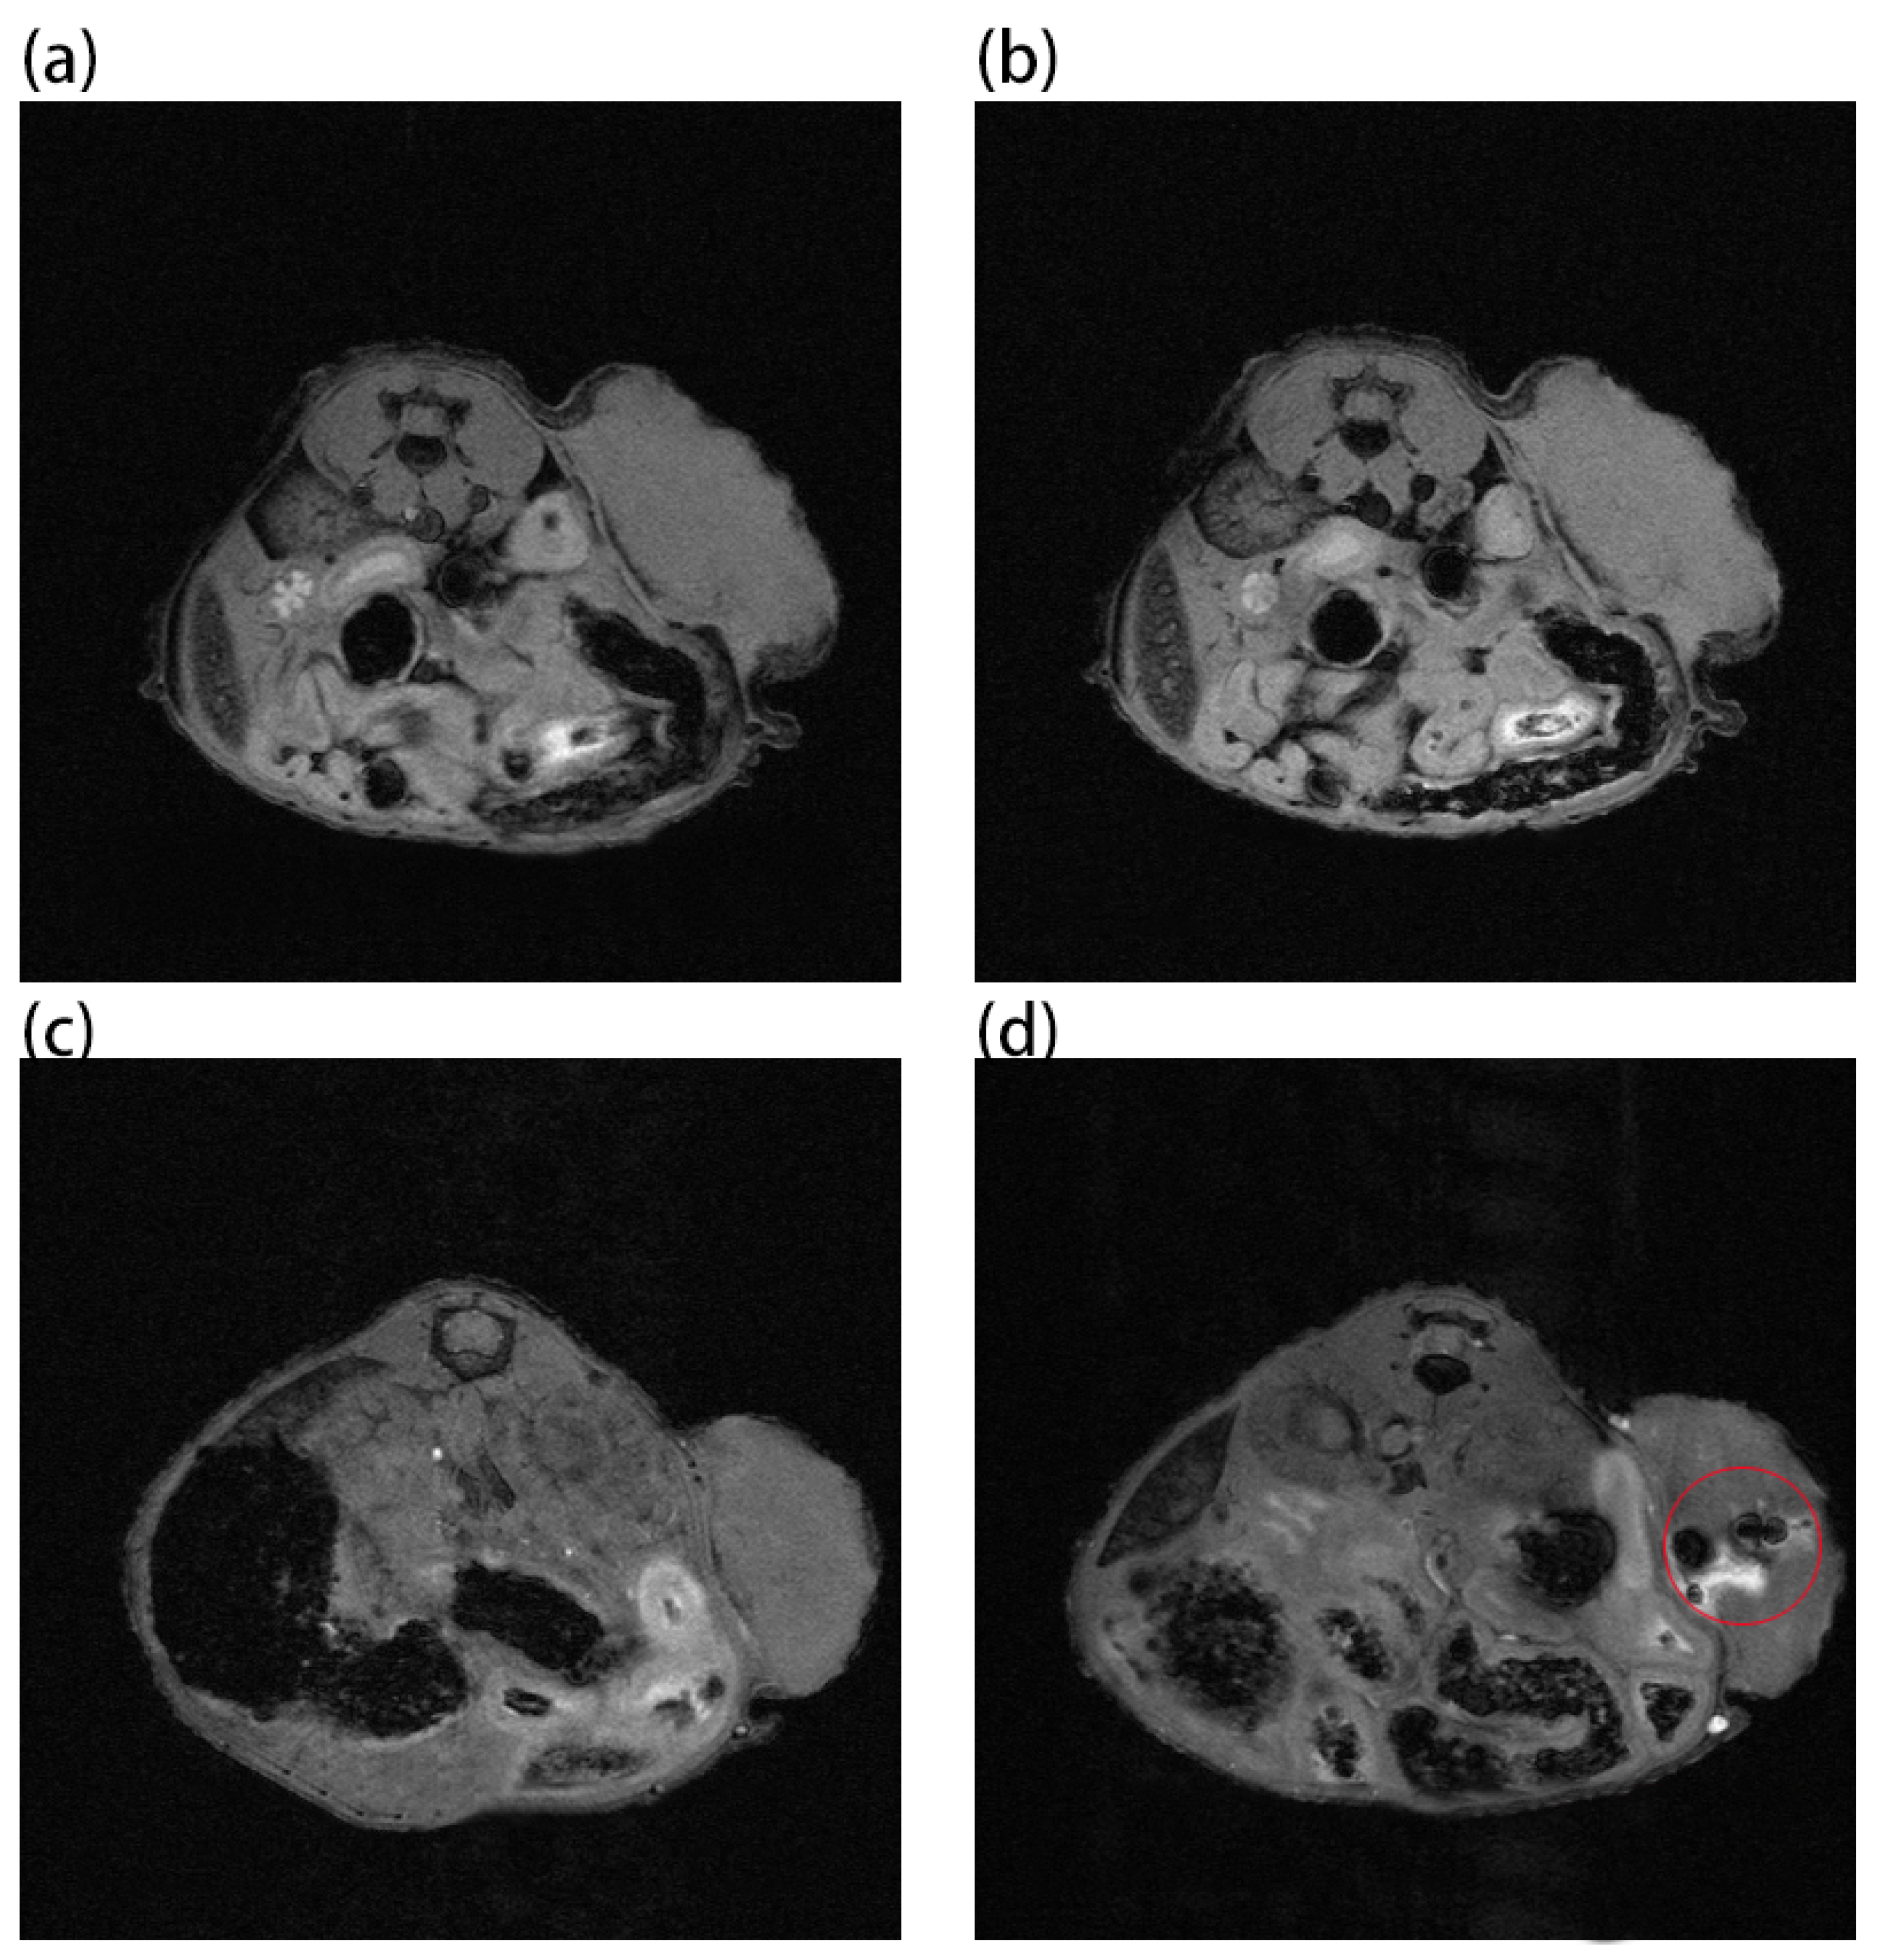

2. Results and Discussion

3.6. MRI, PAI, and CT Imaging of Mice